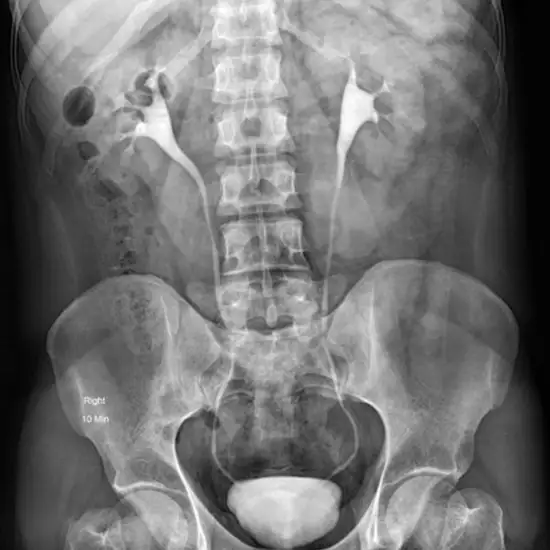

An intravenous urography (IVU) is a test used to assess the internal structure of the urinary system (kidney, bladder, ureters. It is also known as intravenous urogram and intravenous pyelogram (IVP).

What is the procedure for Intravenous Urography (IVU) Test?